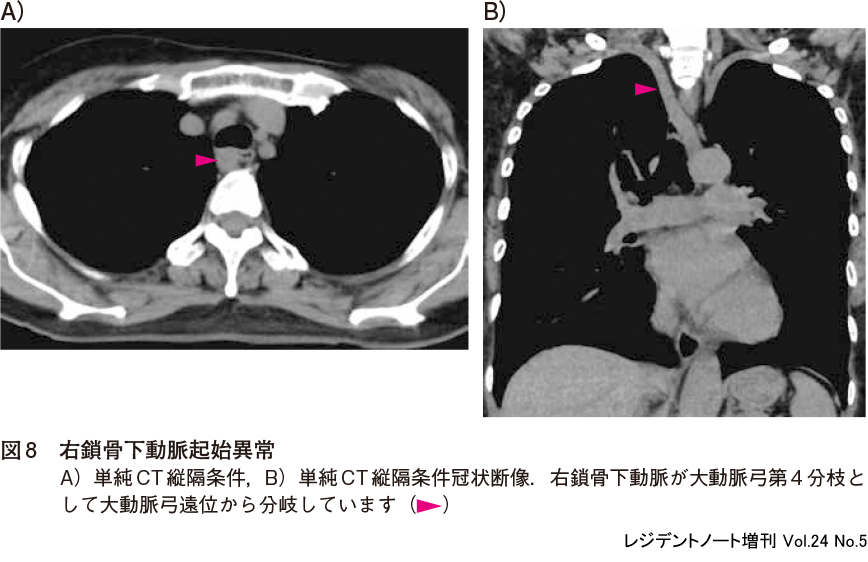

1)右鎖骨下動脈起始異常

右鎖骨下動脈起始異常(aberrant subclavian artery)は,右鎖骨下動脈が大動脈弓の第4分枝として大動脈弓遠位から分岐し,通常食道の後面を走行します(図8).頻度の高い大動脈弓の正常変異で,病的意義はありません.